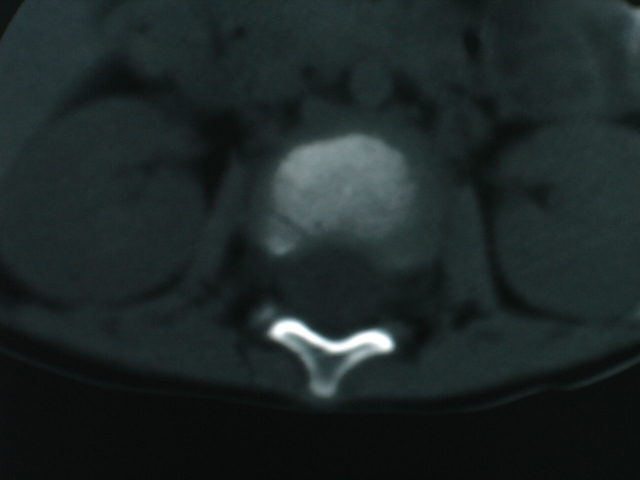

椎体周围见类软组织密度影,椎体见虫蚀样破坏,考虑tb.性。

椎体骨质破坏,椎体周围见软组织密度影.椎体结核

椎体结核合并冷脓肿形成。

我本人也考虑椎体结核,但这么小的年龄的还是第一次见.这个小孩的父母不在家,父母是否有结核也不清楚.

椎体破坏明显,周围软组织肿胀,椎间盘未见明显受累.考虑椎体结核合并冷脓肿形成。

体破坏明显,周围软组织肿胀,椎间盘未见明显受累.考虑椎体结核合并冷脓肿形成.注意排除嗜酸性肉芽肿